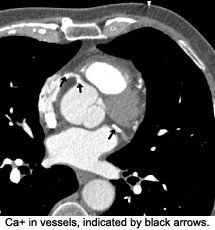

Cardiac CT is particularly useful for detecting high densities in the body; for example, calcium in vessels. Calcium scoring is a technique whereby the extent of calcification in the coronary arteries is measured and scored. It has been around for many years and was initially performed using electron-beam CT (EBCT). This technique is now increasingly performed using multi-slice CT, which is a faster scanner and is considered more accurate. Programs have been designed to identify Ca+ in lesions at a specific threshold, i.e., 130 Hu. The lesion score is calculated by multiplying the lesion area by a density factor derived from the Hounsfield unit (Hu) within this area. For example, a density factor of 1 is assigned for lesions with a maximal density of 130-199 Hu; a density factor of 2 for lesions 200-299 Hu; 3 for lesions 300-399 Hu; and a density factor of 4 for lesions > 400 Hu.

A total calcium score is derived by summing individual lesion scores from each of four anatomic sites (left main, left anterior descending, circumflex, and right coronary arteries). This calculation becomes the calcium score. There is a direct correlation between the extent of calcium in the coronary arteries and the risk of a future cardiac event (heart attack). For example, a calcium score of more than 400 is considered severe, and it would be necessary to take steps to prevent further advancement of atherosclerosis and plaque formation. The higher the calcium score, the more likely there is severe stenosis. On the other hand, a calcium score of 0 does not rule out the existence of soft plaques, but statistically rules out significant coronary artery disease. Though the calcium score does not allow us to evaluate the incidence of soft plaques, it does alert us to the presence and extent of CAD. The higher the calcium score, the more likely soft plaques are present. (Remember that the rupture of a soft plaque is the most common cause of acute coronary syndrome.)2